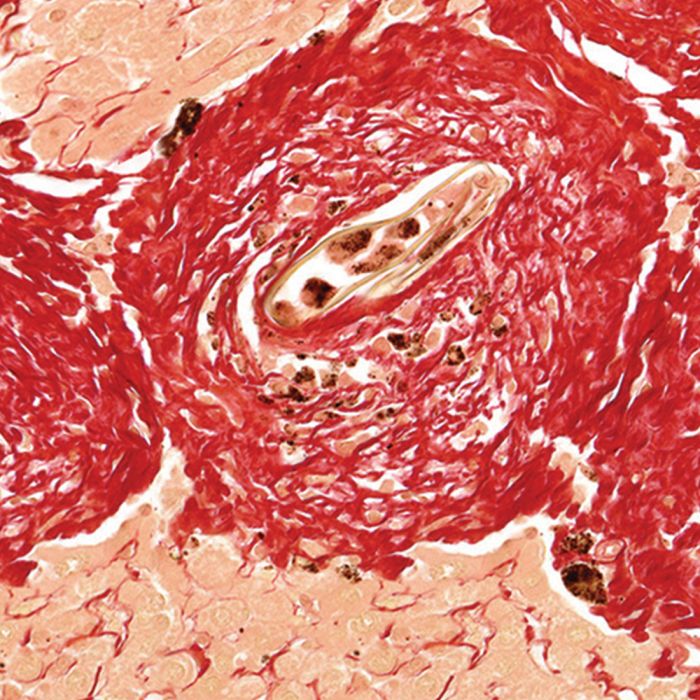

Collagen Type I and III Staining

Our Picrosirius Red Stain binds specifically to collagen fibrils of varying diameter that is used to distinguish collagen Type I from Type III. Picrosirius Red Stain will quantify the amount of collagen in a given area of myocardial tissue. (i.e. the collagen area fraction)

Collagenous structures of the mandible stain brilliant red. Unlike sections stained with hematoxylin and eosin alone, dentinal tubules, Sharpey's fibers and other structures can be seen clearly after using Picrosirius Red Stain procedure. Under polarized light, collagen fibers can be specifically identified and their orientation determined.